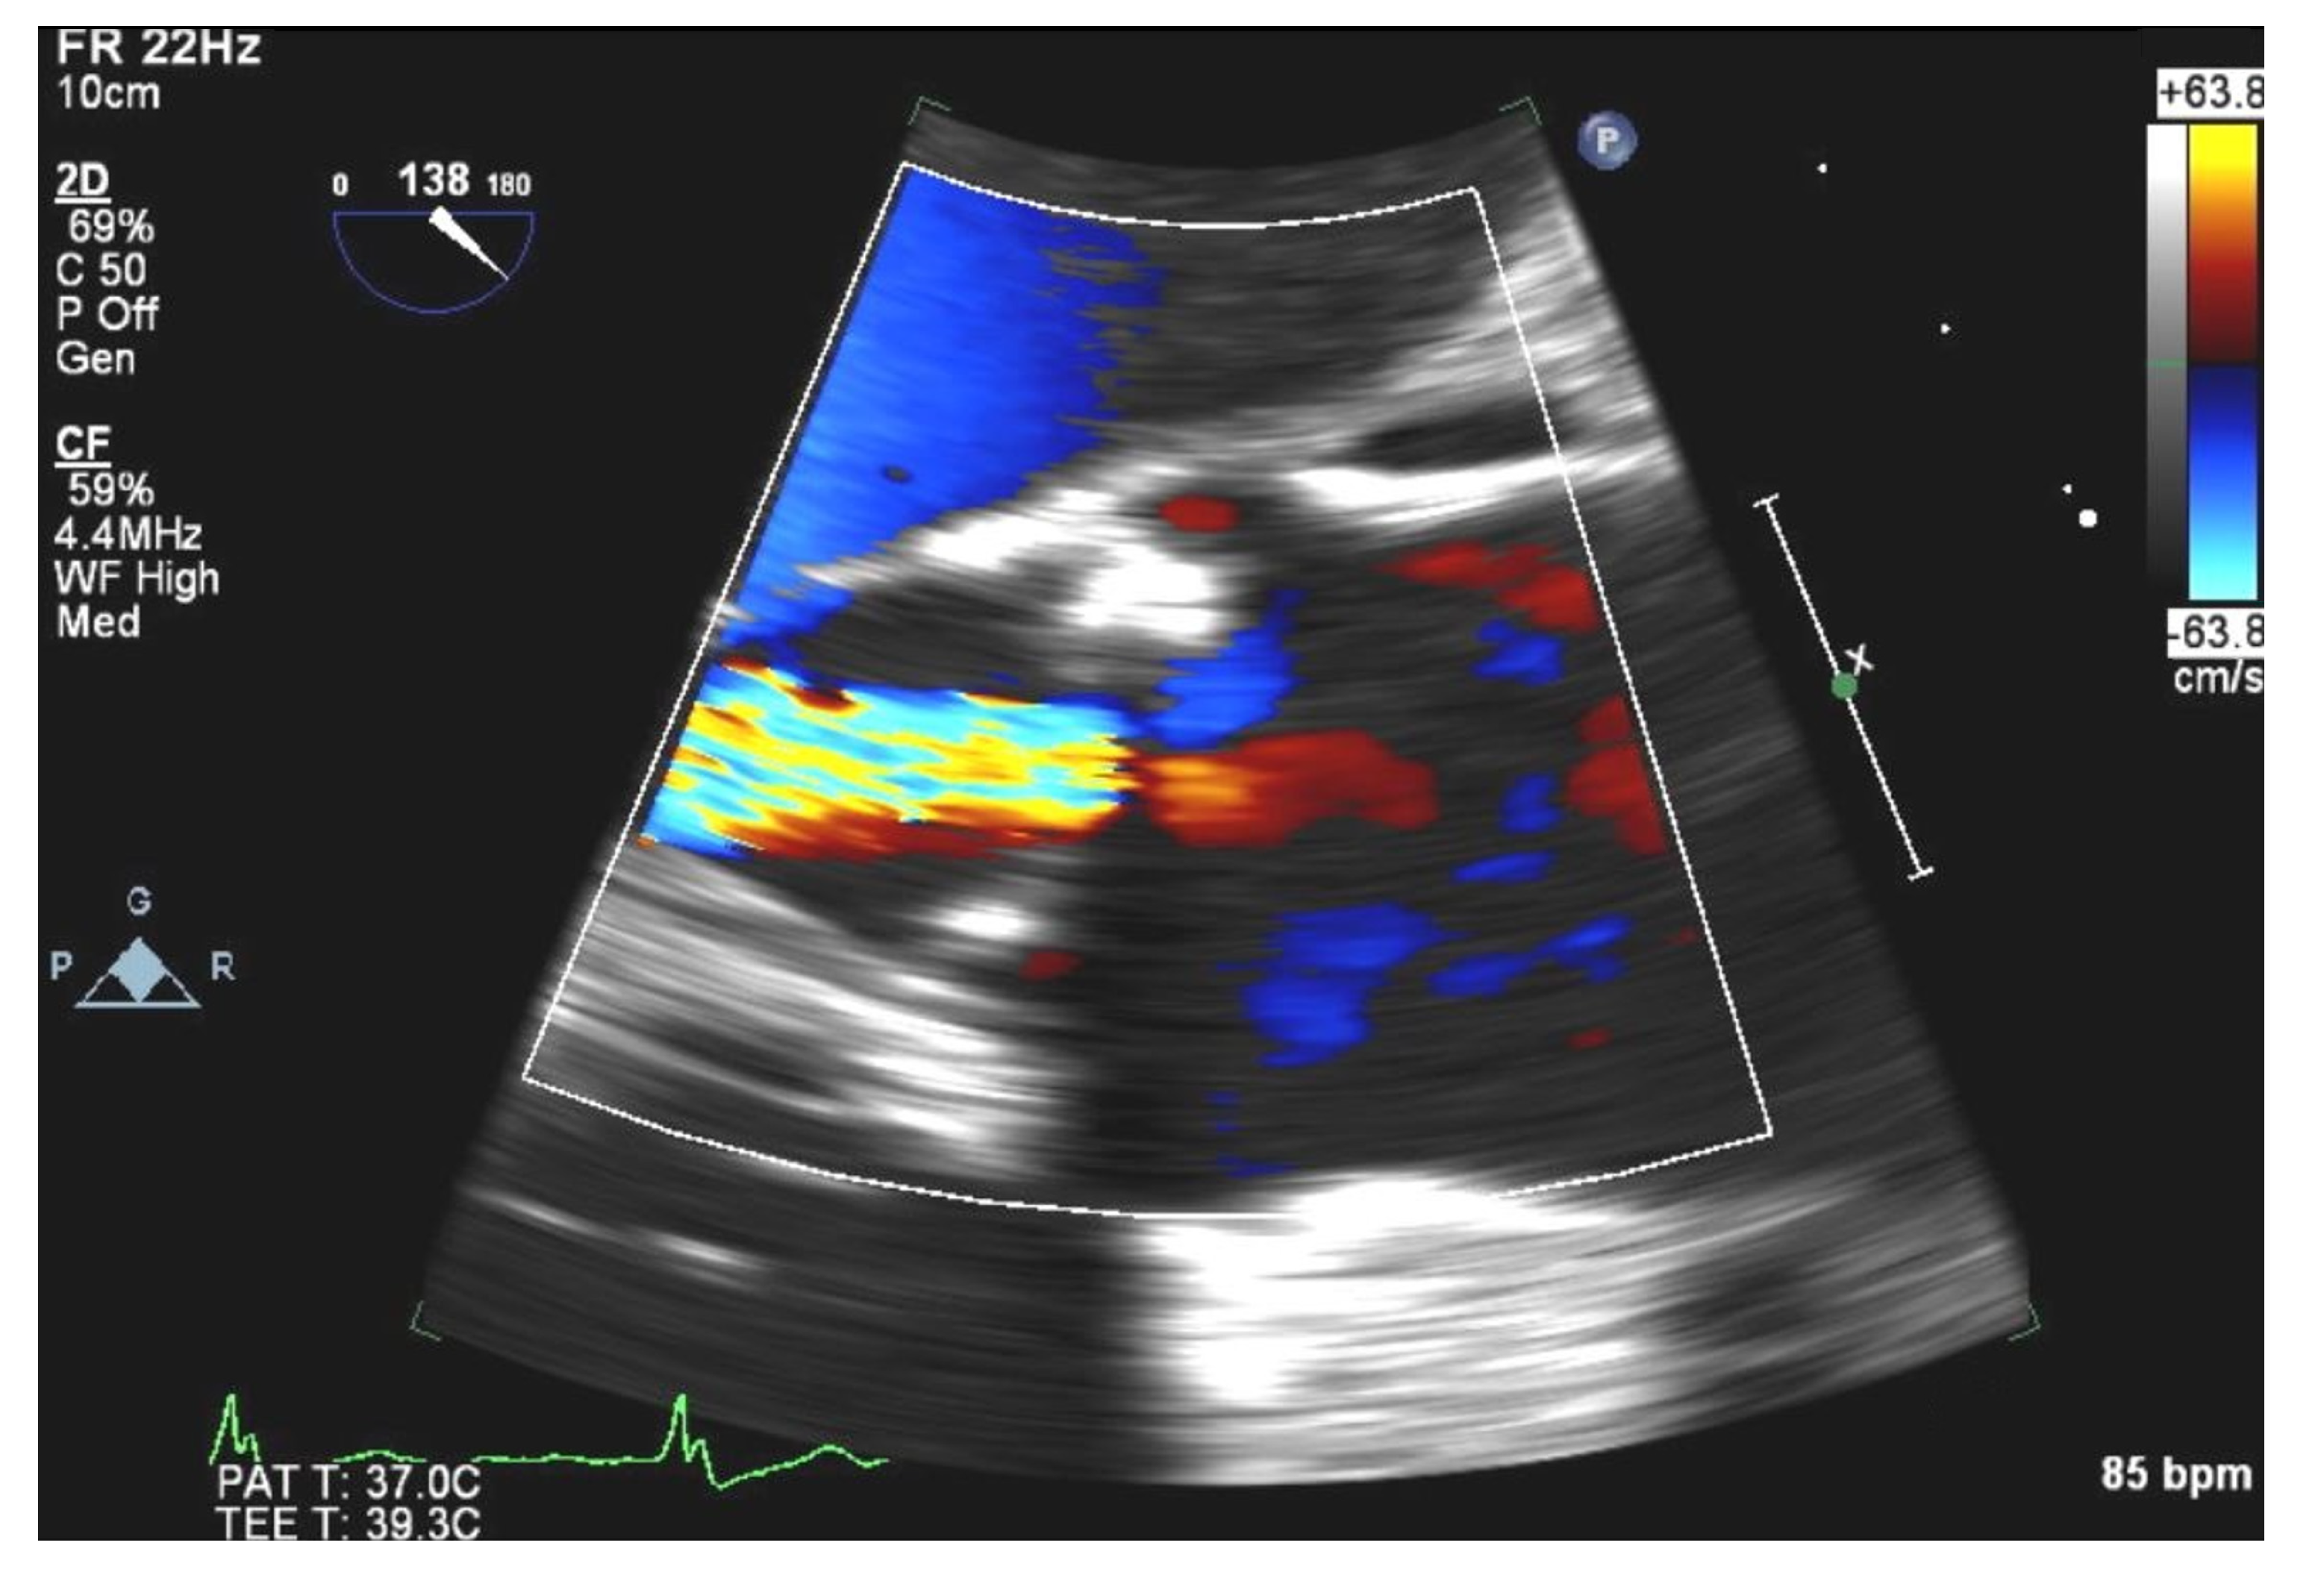

2. Case Presentation